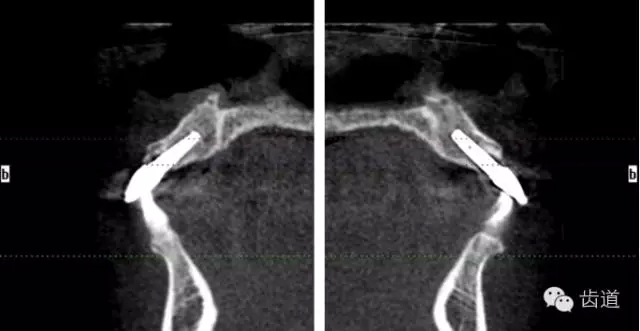

術(shù)前放射片

術(shù)后CT

戴牙后CT

放射檢查:11,21根中三分之一至根尖三分之一處折斷。